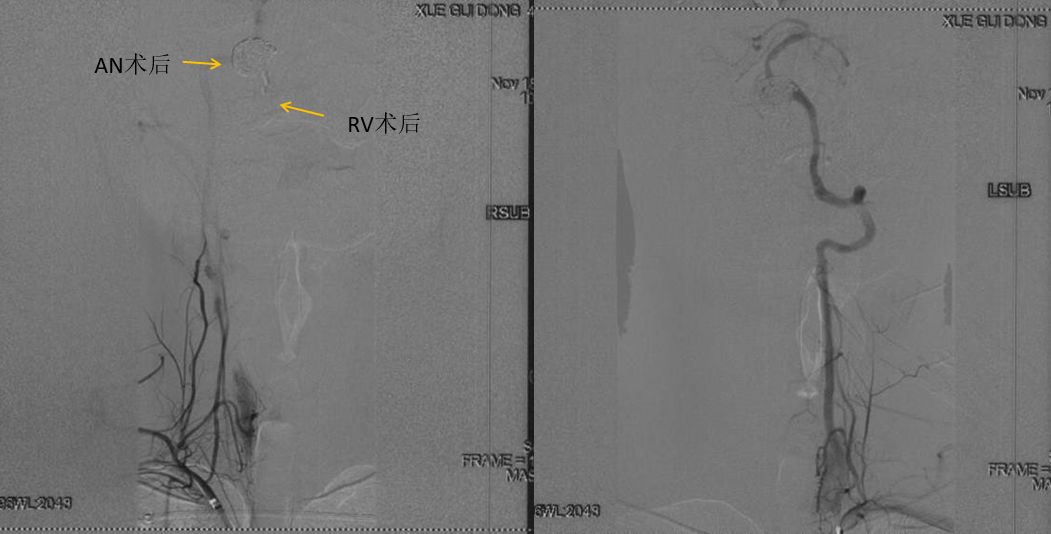

图9 双侧锁骨下造影示右椎动脉和AN栓塞满意,左侧椎动脉血供良好